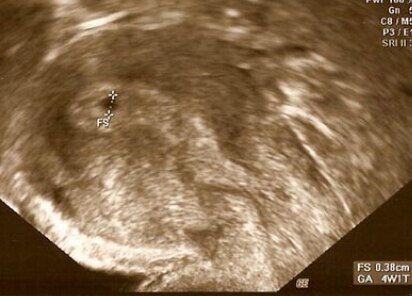

So einen kuriosen punkt meinte ich

Bild zu

Es steht doch auch auf dem Bild FS - fruchtsack. Die grösse wäre doch für 4+1 oder 2 ok. Meine war bei 4+6 10,1mm - also grad mal 1cm. Das passt doch bei dir. Du bist einfach schon weiter im Zyklus als du denkst.

Also, der Test ist positiv (vergiss den 10er, die sind oft Schrott und zeigen schlechter an als 25er) und der kuriose Punkt ist aber eine Fruchthülle! 1. steht da doch definitiv FS (Fruchtsack) und sogar das daraus errechnete SS-Alter (alles unten rechts). Passt doch auch zu deinem Zyklus und deiner Rechnung dazu. Und es ist möglich (lt. meinem FA), eine Minifruchthülle vor NMT zu sehen (kenne auch einige) 2. meine ich um die Hülle diesen "Ring" zu erkennen, den man am Anfang total gut sieht (ich glaube, mein FA sagte mal, das ist so eine Verdickung v. Gelbkörperhormon oder so) und der sehr wichtig ist. Sieht eigentlich sehr schön aus. Ich denke, dein FA hat einfach gesagt, abwarten, da du noch sehr früh dran bist und es sich alles erst fest einnistet (oder eben vielleicht leider nicht). In so einem frühen Stadium will er wahrscheinlich nicht mehr sagen bzw. sich gar festlegen. Also, positiv denken und fest daran glauben, dass es sich weiter entwickelt. Alles Gute! lg Sandra

... Das selbe Bild findet man, wenn man bei Google Ultraschall 5. Woche eingibt... Nur das auf dem Bild der AP das Datum abgeschnitten. Ist http://www.wunschkinder.net/schwangerschaft/ultraschall/5-woche/ Bei ES+8 (viel weiter kannst du nicht sein, wenn du am Miiwoch deine Mens erwartet) ist es sehr unwahrscheinlich positiv zu testen und definitiv sieht man rein gar nix im Ultraschall... Bin selbst gerade in der Frühschwangerschaft und gucke immer mal was man so gerade sehen könnte im Ultraschall und so bin ich darauf gestoßen..

Hat auch niemand behauptet ... Wollte zeigen wie der "punkt" war ... da steht von mir geschrieben: so einen kuriosen punkt meinte ich... Und nicht : hier ein bild von mir... Ja wenn du meinst ;) ich weiß dass ich 2 tests vor mir liegen hab die sind positiv wenn auch nur ganz leicht... und ja da wird mein frauenarzt und ich uns wohl oder übel versehen haben ;) Mal gucken ob der punkt größer wird... würde jtz in der vierten woche sein... wie bei meknen andern 3 kindern auch... nur da war die fruchthöhle größer und der arzt meinte als man in der 5. Schon den embryo sah das mein eisprung wahrscheinlich früher war.. Schlaumeier ;)